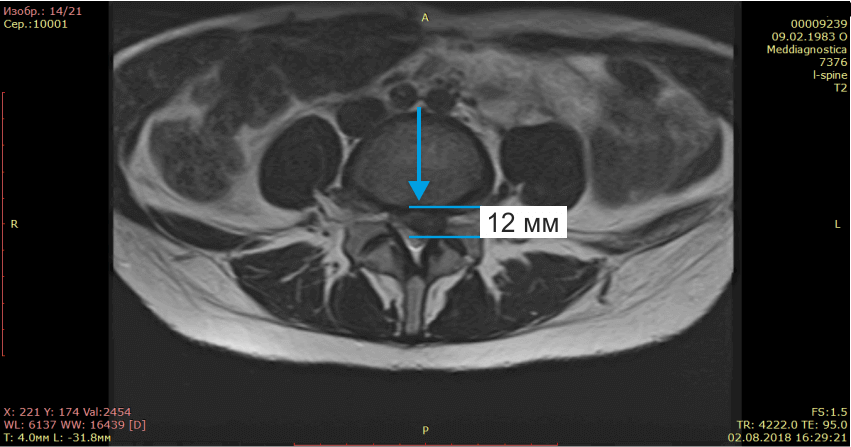

Осмотрели Ирину неврологически и ортопедически, исследовали позвоночник на МРТ и рентгене. Оказалось, что у нее очень большая левосторонняя грыжа размером 12 мм.

На МРТ показано излечение грыжи диска (до- и после лечения).